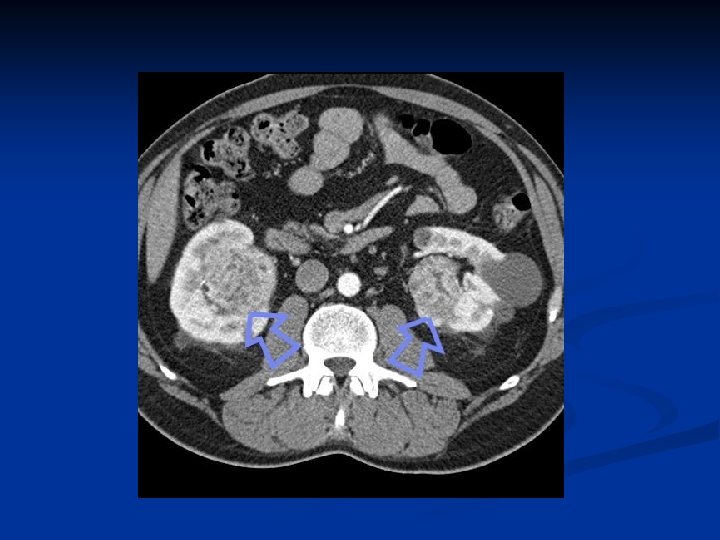

Investigations Diagnosis can often be confirmed by renal ultrasound n CT scanning allows assessment of renal vein and caval spread n Echocardiogram should be considered if clot in IVC extends above diaphragm n

RCC with IVC thrombus

Male : female ratio is approximately 2: 1 n Increased incidence seen in von Hippel. Lindau syndrome. n Pathologically may extend into renal vein and inferior vena cava n Blood born spread can result in 'cannon ball' pulmonary metastases n